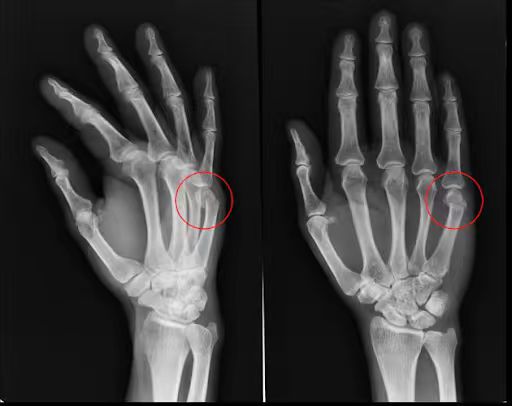

2.舟状骨骨折

位于大拇指下方的舟状骨在手腕撑地时极易受损。这种骨折非常棘手,因为舟状骨的血液供应相对匮乏。这种骨折极难愈合,处理不当可能导致永久性的关节炎或骨坏死。(许多网球和高尔夫运动员因这种隐匿性骨折而导致职业生涯巅峰缩短,因为该部位关系到手腕的精细转动。)